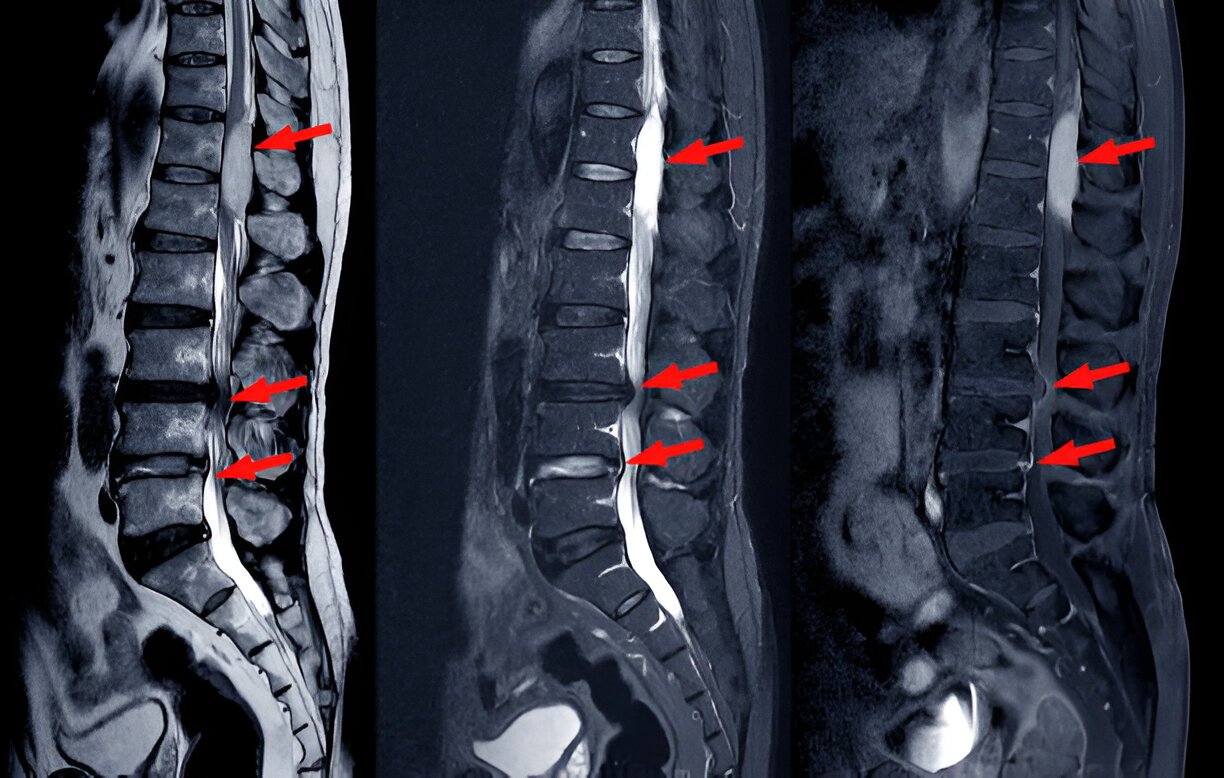

Canal stenosis in lumbar spondylitis refers to the narrowing of the spinal canal in the lower back (lumbar region) due to inflammation and degenerative changes in the spine. This narrowing puts pressure on the spinal cord and nerves, causing pain, tingling, or even weakness in the legs.

Canal Stenosis – narrowing of the spinal canal, which compresses nerves and causes neurological symptoms.